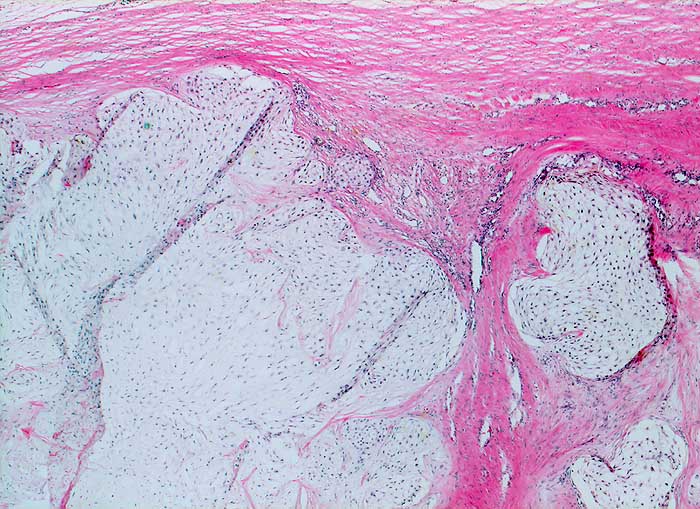

Chondrosarkom

Der lobulierte chondroid differenzierte Tumor infiltriert die Weichteile der Thoraxwand. Das Sarkom ist deutlich zellreicher als normaler Knorpel vor allem in den Randpartien der Lobuli.

Makroskopischer Befund des Thoraxwandteilresektates: halbkugeliger Tumor (7,5x7x3,6cm). Auf Schnitt findet sich ein gallertiger, teils knorpeliger Tumor mit Nekrosen und Einblutungen. Tumor durch die beiden mittleren Rippen durchtretend.

Brustwandtumor parasternal rechts Teils extra-, vorwiegend intrathorakal